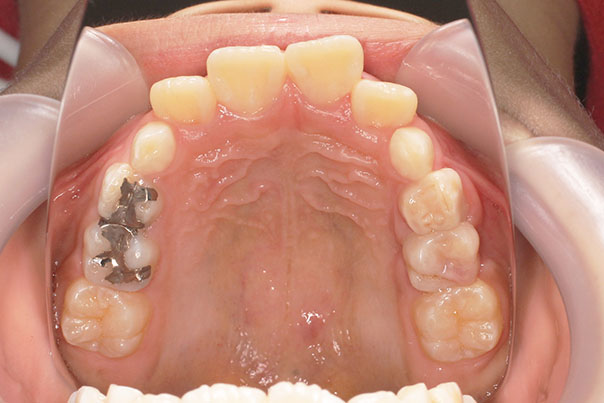

歯が重なっている、出っ歯を治したい 以前に治療した方からの紹介で来院した患者さんです。 上下顎前歯部の叢生(がたつき)、上下顎前歯の前方傾斜、 骨格的上顎前突傾向でした。 小児矯正で叢生の緩和を行い、 本格矯正で前方傾斜した前歯の改善を行いました。 マルチブラケット 動的治療期間 3年3か月 調整回数25回